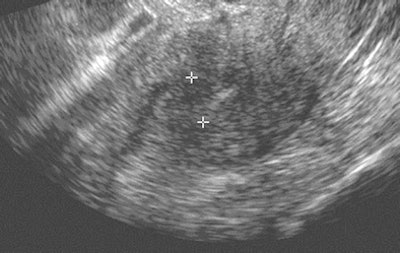

| Sixty-two-year-old woman with abnormal endometrium. Transvaginal sonogram (above) and axial contrast-enhanced CT image (below) show thickened endometrium in postmenopausal patient. Calipers (above) indicate thickness of endometrium. Images courtesy of the American Roentgen Ray Society; from Grossman J, Ricci Z, Rozenblit A, et al. Efficacy of contrast-enhanced CT in assessing the endometrium. AJR. 2008;191:664-669. |